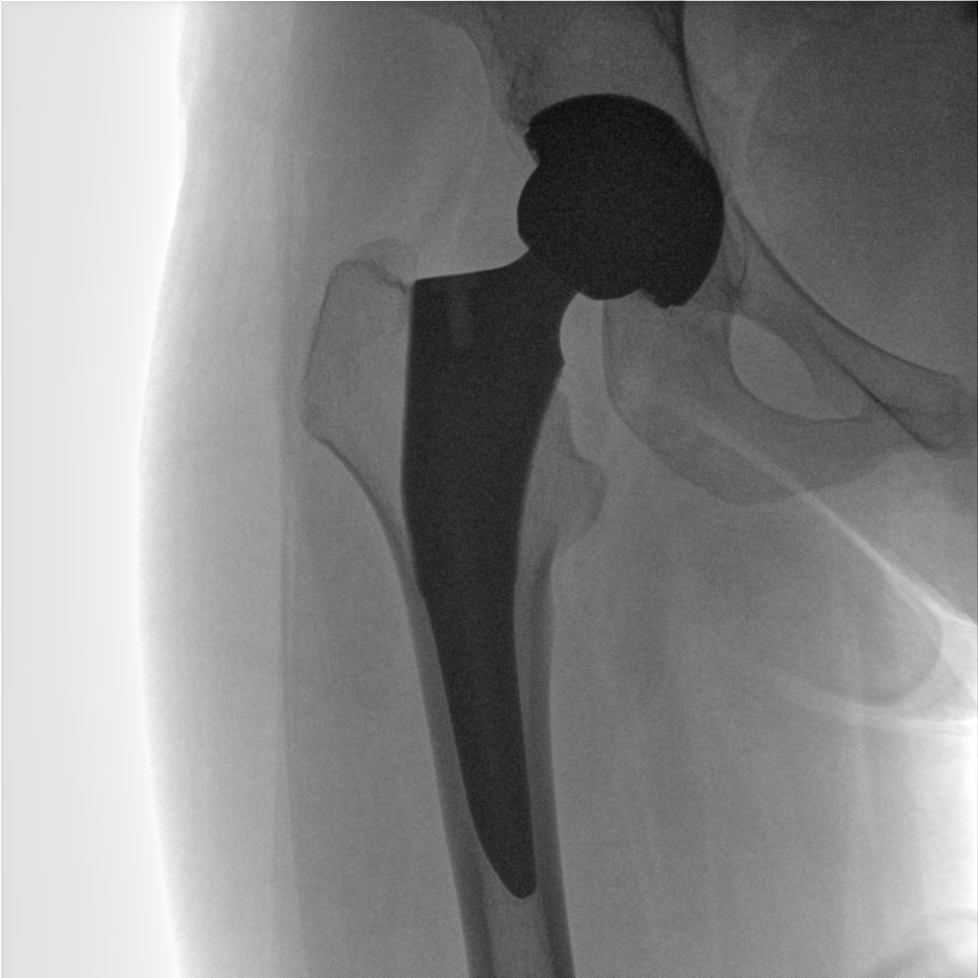

術(shù)中三維成像和橫斷面圖像提供多角度的手術(shù)診斷信息,輔助醫(yī)生進行術(shù)中評估判斷,諸如骨折復(fù)位情況和內(nèi)植入螺釘?shù)某叽绾臀恢?,輔助手術(shù)更好地完成。